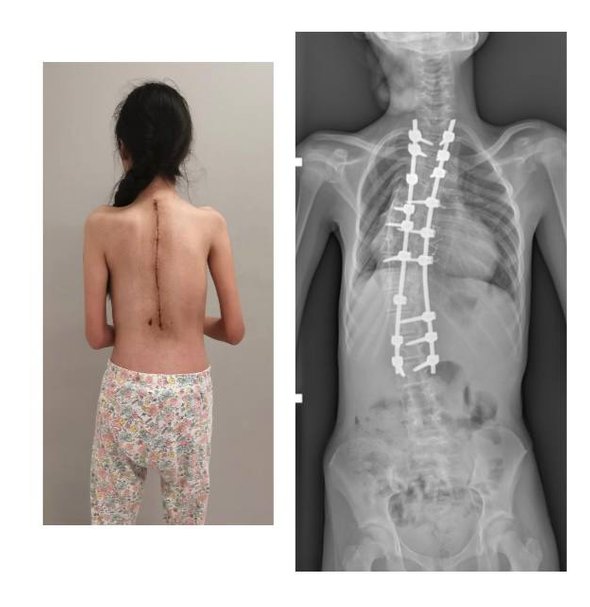

По словам медиков, у пациентки из Омской области наблюдался выраженный сколиоз грудного отдела позвоночника, который стремительно прогрессировал и привел к развитию дыхательной недостаточности. Деформация сопровождалась значительным перекосом плечевого пояса: левое плечо у ребенка было на 10 сантиметров ниже правого, отмечался ярко выраженный реберный горб. Угол деформации самого позвоночника составлял 115 градусов.

«В тела позвонков со второго грудного по третий поясничный мы установили транспедикулярные винты, которые впоследствии соединили между собой стержнями. Затем постепенно изменили ось позвоночника в трех плоскостях, за счет чего и добились коррекции. На протяжении металлоконструкции уложили костный аутотрансплантат, чтобы обеспечить ее максимальную стабильность в будущем», — рассказал хирург-вертебролог отделения травматологии и ортопедии Андрей Пантелеев.

В результате специалисты добились желаемого результата хирургического вмешательства. Дисбаланс плечевого пояса и реберный горб был полностью устранен, а угол деформации не превысил 40 градусов.

фото: t.me/RDKBofficial